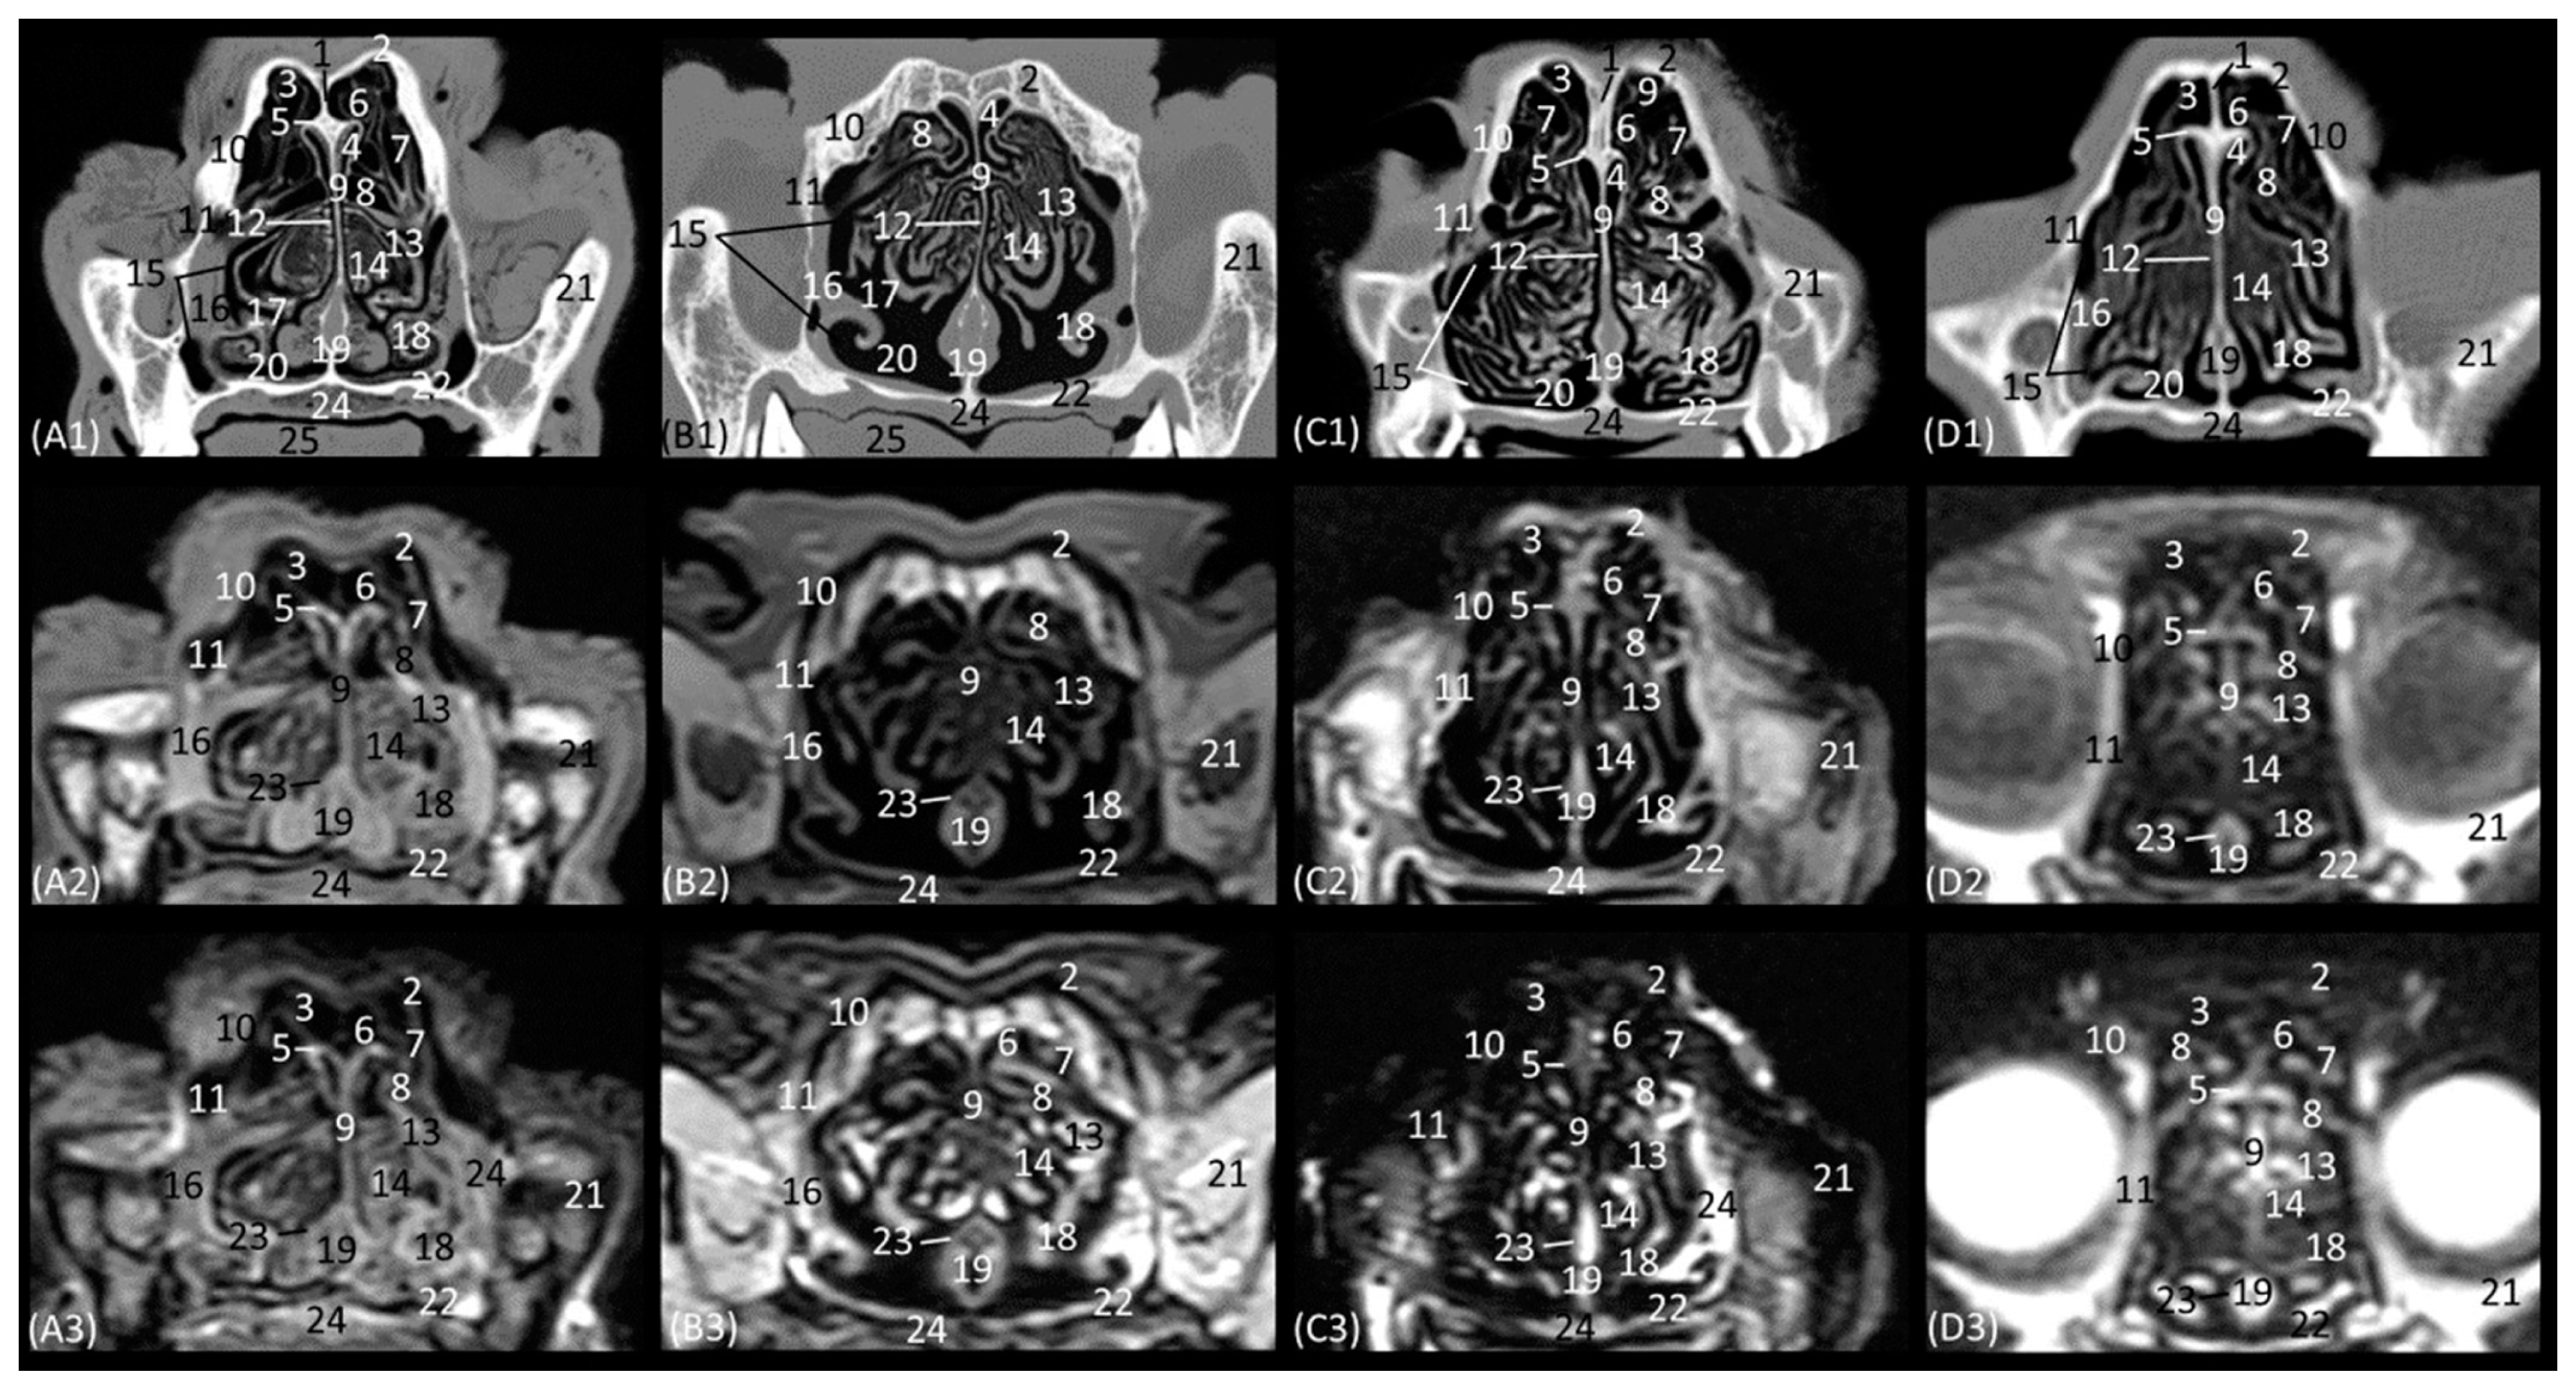

Figure 12(A1–D3) represents a ventral horizontal view of the nasal cavity that sections the entire zygomatic arch, the temporal process of the zygomatic bone, as well as the zygomatic process of the temporal bone, although the latter is observed only in the leopard and the cheetah in the study by CT. The maxillary bone was left without rostral continuation in leopard, lion, and cat while in the cheetah, it continued with the incisive bone rostrally. In the nasal cavity, the alar fold, the ventral nasal concha, the third and the fourth endoturbinates, the nasal cavernous plexuses, and the lateral nasal gland were observed. The alar fold was still identified at this level, but in the lion, the basal fold was also visible. The lateral nasal gland was visible in this section in all four species in an area of soft tissue close to the lacrimal bone, which was identified as hypoattenuated on CT and hypointense on MRI with respect to the bone. On the other hand, the sphenoid sinus can be identified in the leopard and the cheetah, although it does not appear in the lion or the cat. Furthermore, at this level and caudal to the fourth endoturbinate, we can identify the sphenoid sinus with a thin septum that was hyperattenuated on CT and hyperintense on MRI in the leopard, cheetah, and cat, but it was not evident in the lion on both CT and MRI, nor in the cat on CT. Finally, unlike the other species, the nasal cavernous plexuses were highly developed in the cat and a little in the lion, and they were located in the most rostral part of the nasal septum.

Figure 12. Representative dorsal multiplanar reconstruction (MPR) CT (A1D1), T1-weighted MR (A2D2), and T2-weighted MR (A3D3) images at the level of the 3rd and 4th endoturbinates. Level section (C) II. Dorsal images are oriented so that the rostral part is to the top. All views are dorsal. (A1A3): Leopard; (B1B3): lion; (C1C3): cheetah; and (D1D3): cat. 1. Incisive bone; 2. nasal cavernous plexuses; 3. alar fold; 4. common nasal meatus; 5. maxillary bone; 6. ventral nasal concha; 7. nasal septum: cartilage; 8. zygomatic bone; 9. 3rd endoturbinate; 10. 4th endoturbinate; 11. lacrimal bone; 12. lateral nasal gland; 13. presphenoid bone: wing; 14. basisphenoid bone: wing; 15. sphenoidal sinus; 16. zygomatic bone: temporal process; 17. mandible: ramus; 18. ethmoid bone: perpendicular plate; 19. temporal bone: zygomatic process; 20. temporal bone: squamous part; 21. occipital bone: squama.